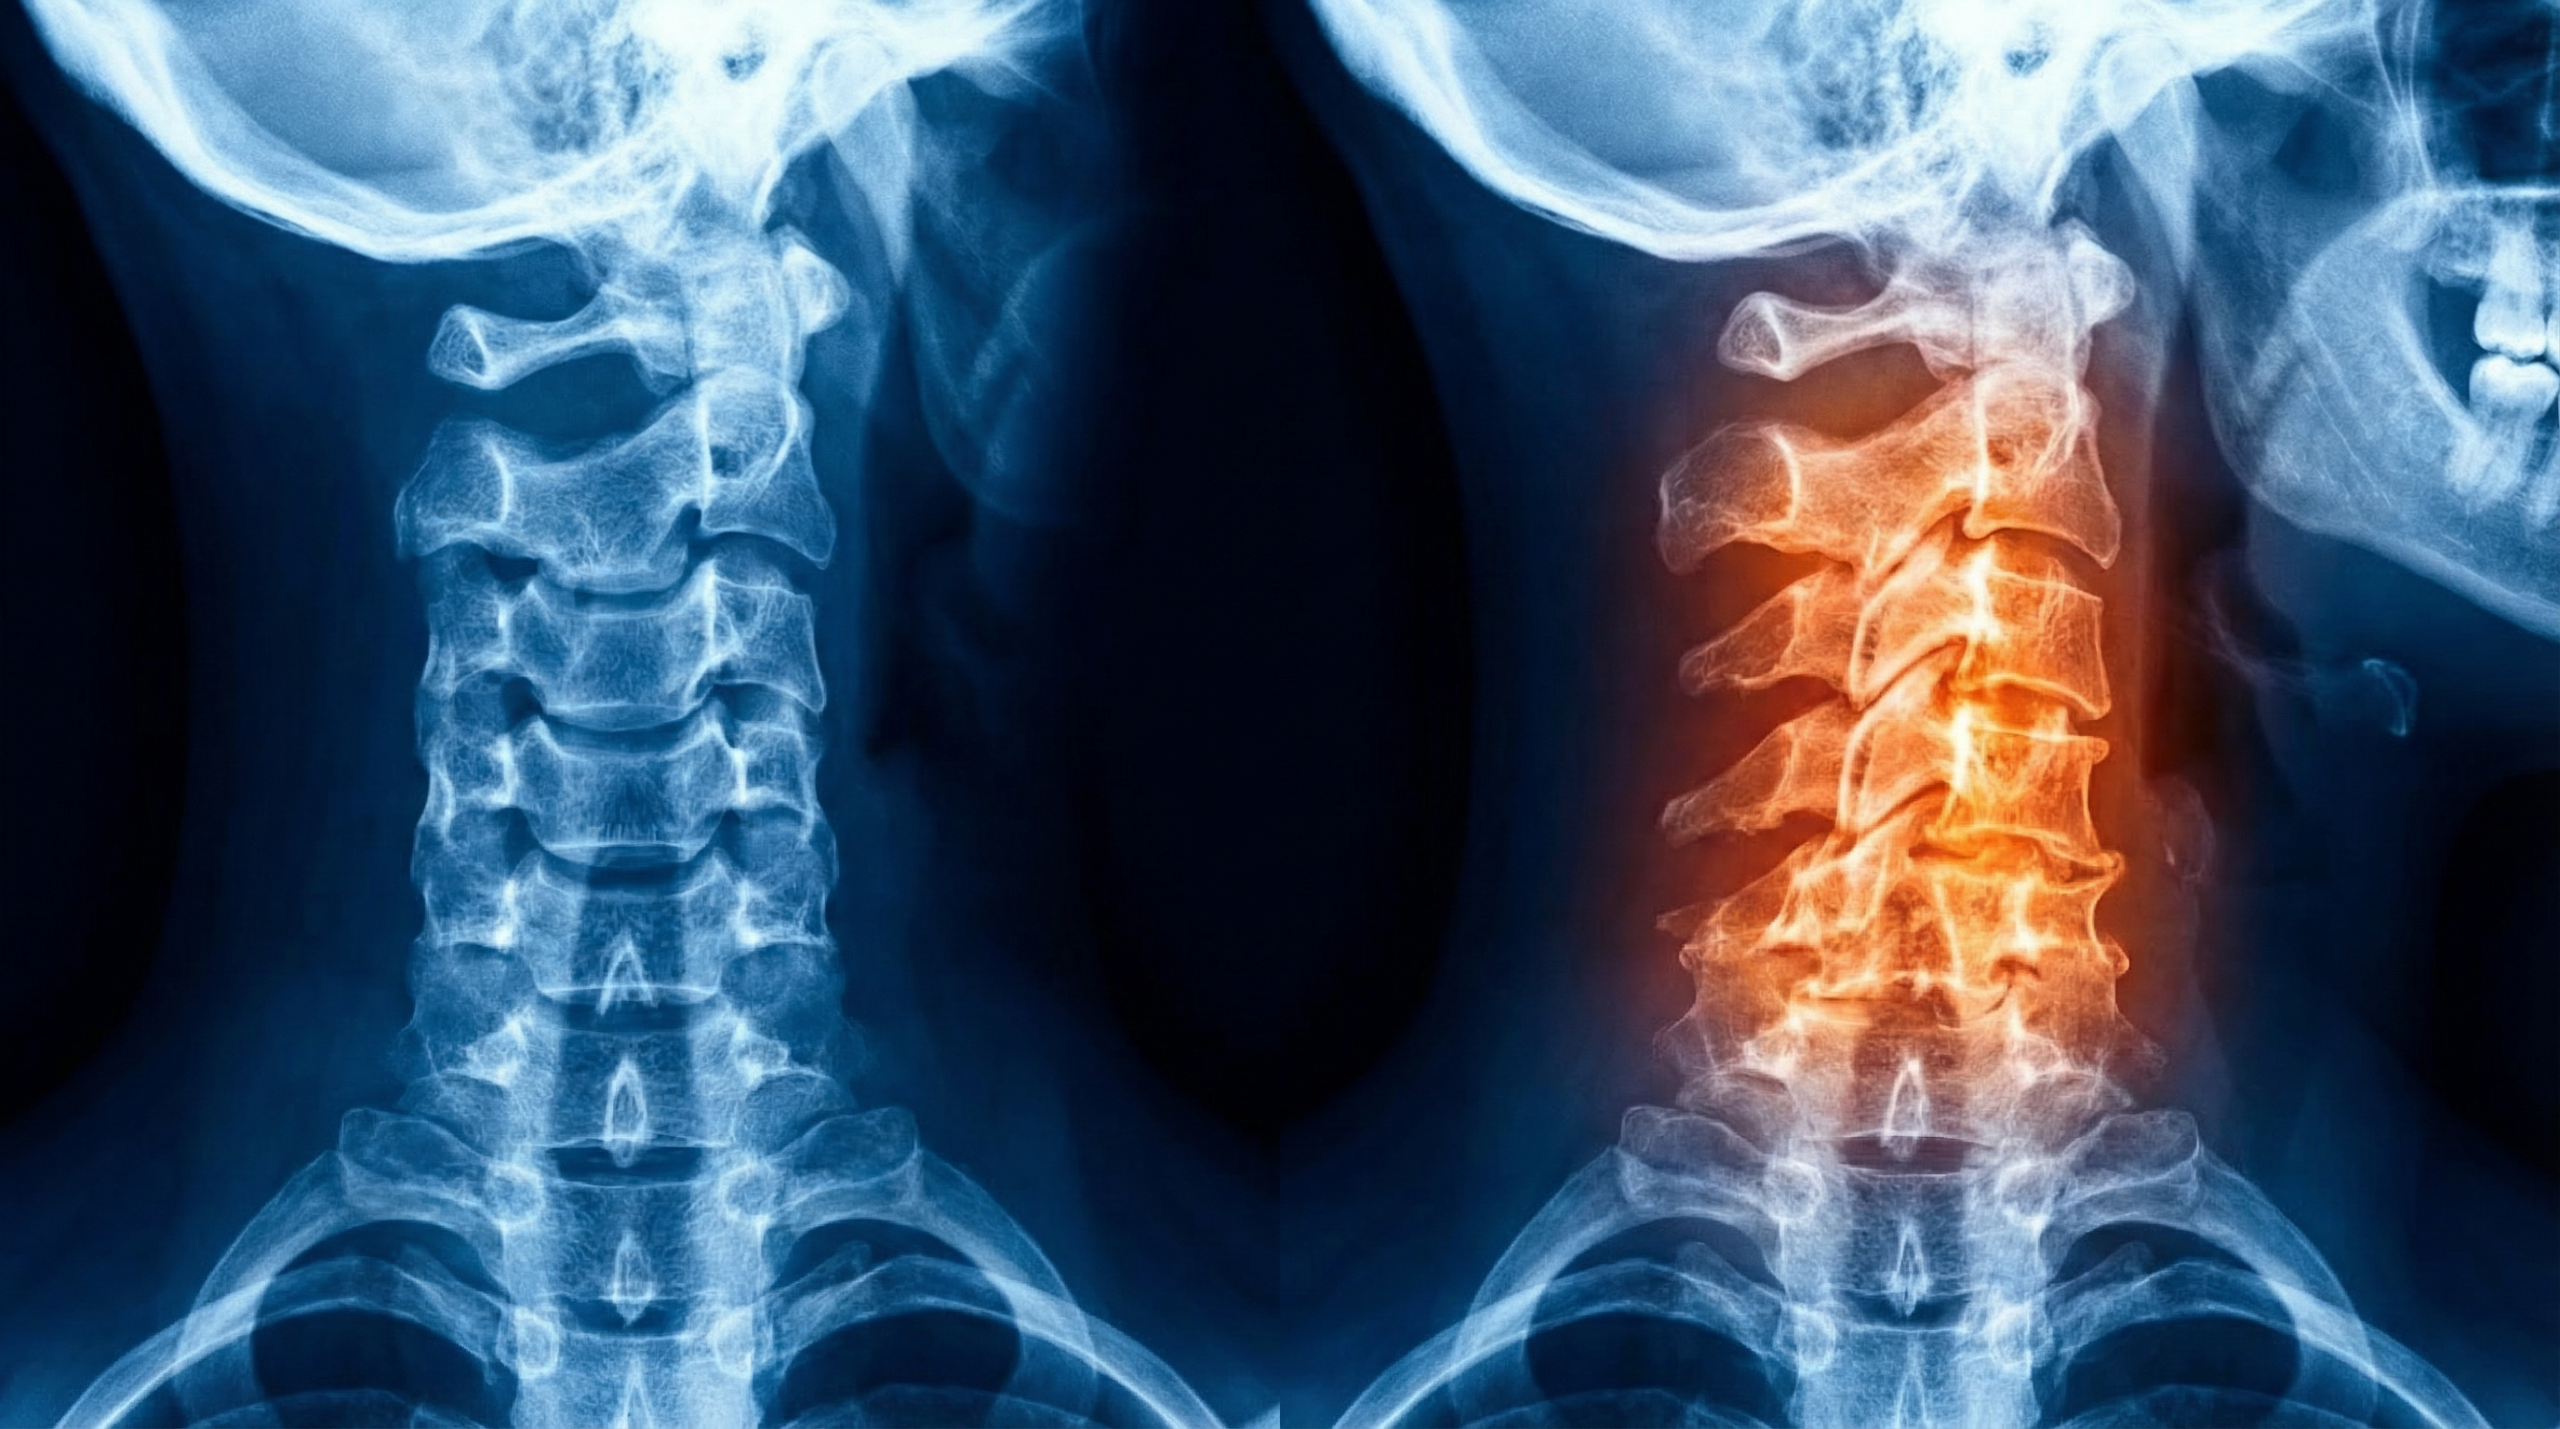

Na jaren van pijnlijke gewrichtsslijtage in mijn nek en het uitproberen van talloze 'oplossingen', weet ik precies hoe slopend artrose nek kan zijn.

Want als je eenmaal last hebt van artrose nek, wil je er alles aan doen om weer normaal te kunnen bewegen zonder die constante nekpijn en stijfheid...

En juist die chronische ontstekingsprocessen en kraakbeenafbraak in je nek zorgen ervoor dat je klachten blijven terugkomen - omdat je lichaam in een constante staat van ontsteking en gewrichtsslijtage verkeert.

Artrose nek is meer dan alleen lokale nekpijn - het is een duidelijk signaal dat je lichaam in een chronische ontstekingstoestand verkeert die je algehele gezondheid aantast.

Nekartrose ontstaat niet zomaar.

Het is het resultaat van chronische ontstekingsprocessen en kraakbeenafbraak in je nek, meestal door een combinatie van factoren die elkaar versterken.

Artrose in je nek is meer dan alleen lokale nekpijn - het is een duidelijk signaal dat je lichaam in een chronische ontstekingstoestand verkeert.